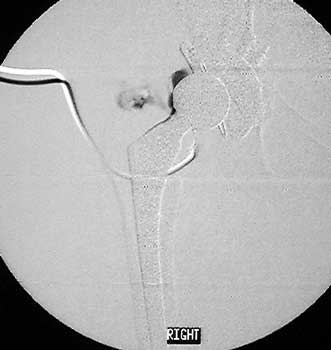

Dry tap secondary to large greater trochanteric bursa, 20

gauge spinal needle placed in bursa under fluoroscopic guidance

Scar with focal area of drainage. Dry tap secondary to large greater trochanteric bursa with

sinus tract draining to skin